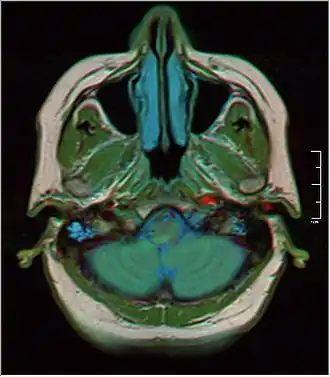

|  MRI showing fluid in mastoid air cells | |